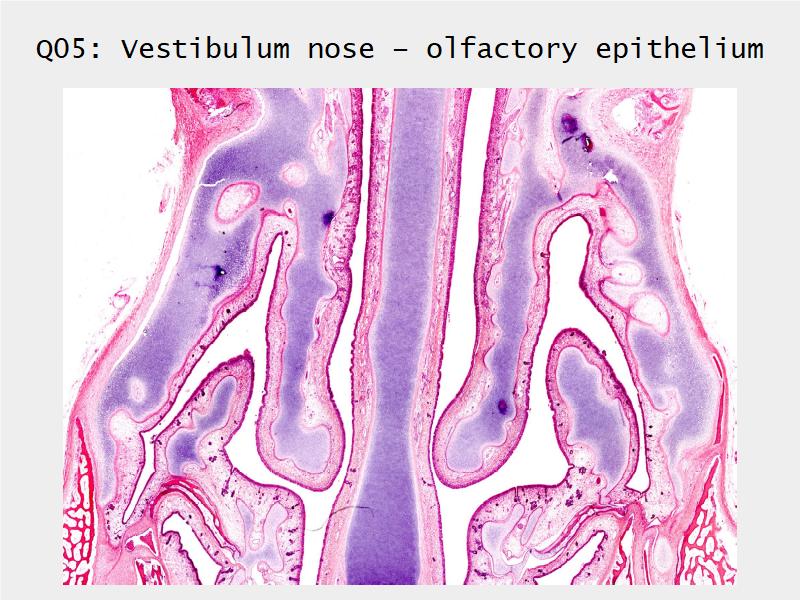

Respiratory Epithelium: Trachea

Respiratory epithelium

- Pseudostratified

- Ciliated

- Columnar

- Epithelium with

- 4 Cells

- Ciliated columnar cells

- Non-ciliated columnar cells

- Goblet cells

- Basal cells